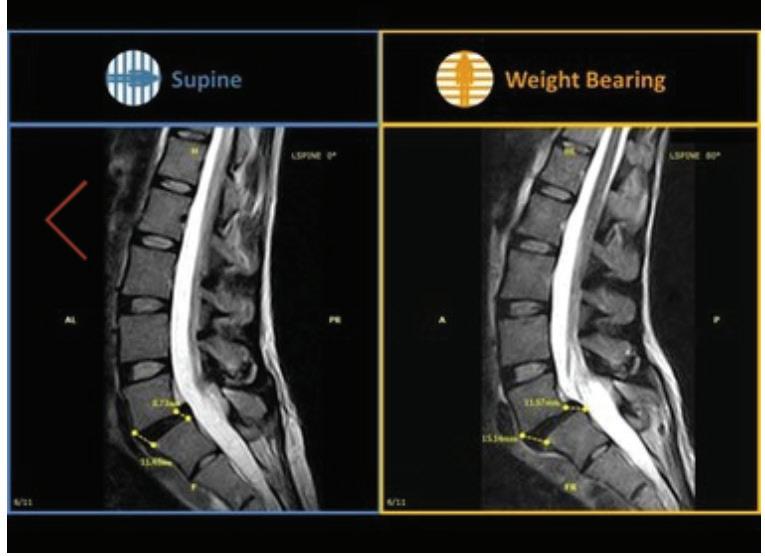

What a weight-bearing MRI reveals vs. a Supine MRI

G-scan Brio Reveals What Supine MRI Misses

Conventional MRI may not demonstrate the pathology related to these symptoms, but G-scan Brio gives you a new point of view so you can accurately diagnose MSK pathologies affected by weight-bearing position.

More Detail, Better Accuracy, Greater Confidence

The G-scan Bro is superior to other MRIs because both the magnet and patient can rotate from 0 to 90 degrees.

G-scan Brio offers a revolutionary MRI approach that increases diagnostic accuracy and confidence for musculoskeletal applications.